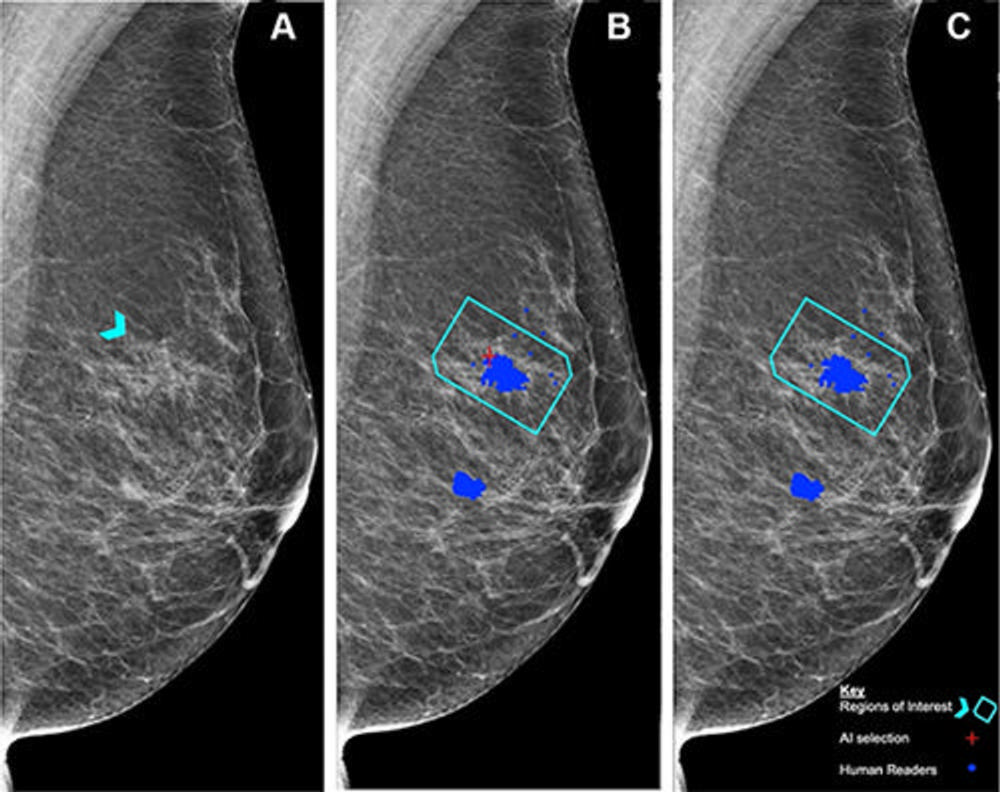

Figure 2. (A) Right mediolateral oblique unadulterated mammogram shows an 8-mm ill-defined mass (arrowhead), which, after biopsy, was determined to be a histologic grade 2 ductal carcinoma of no special type. (B) Mammogram shows findings by human readers (blue areas) and the Lunit INSIGHT MMG artificial intelligence (AI) algorithm (red cross). Each blue dot is a mark placed by an individual human reader on a perceived abnormality when the Personal Performance in Mammographic Screening (PERFORMS) case was read. A region of interest (pentagon) has been annotated by the PERFORMS scheme organizers and their expert radiology panel. AI has correctly marked the region of interest in the right breast for recall. Source: PERFORMS via Yan Chen.